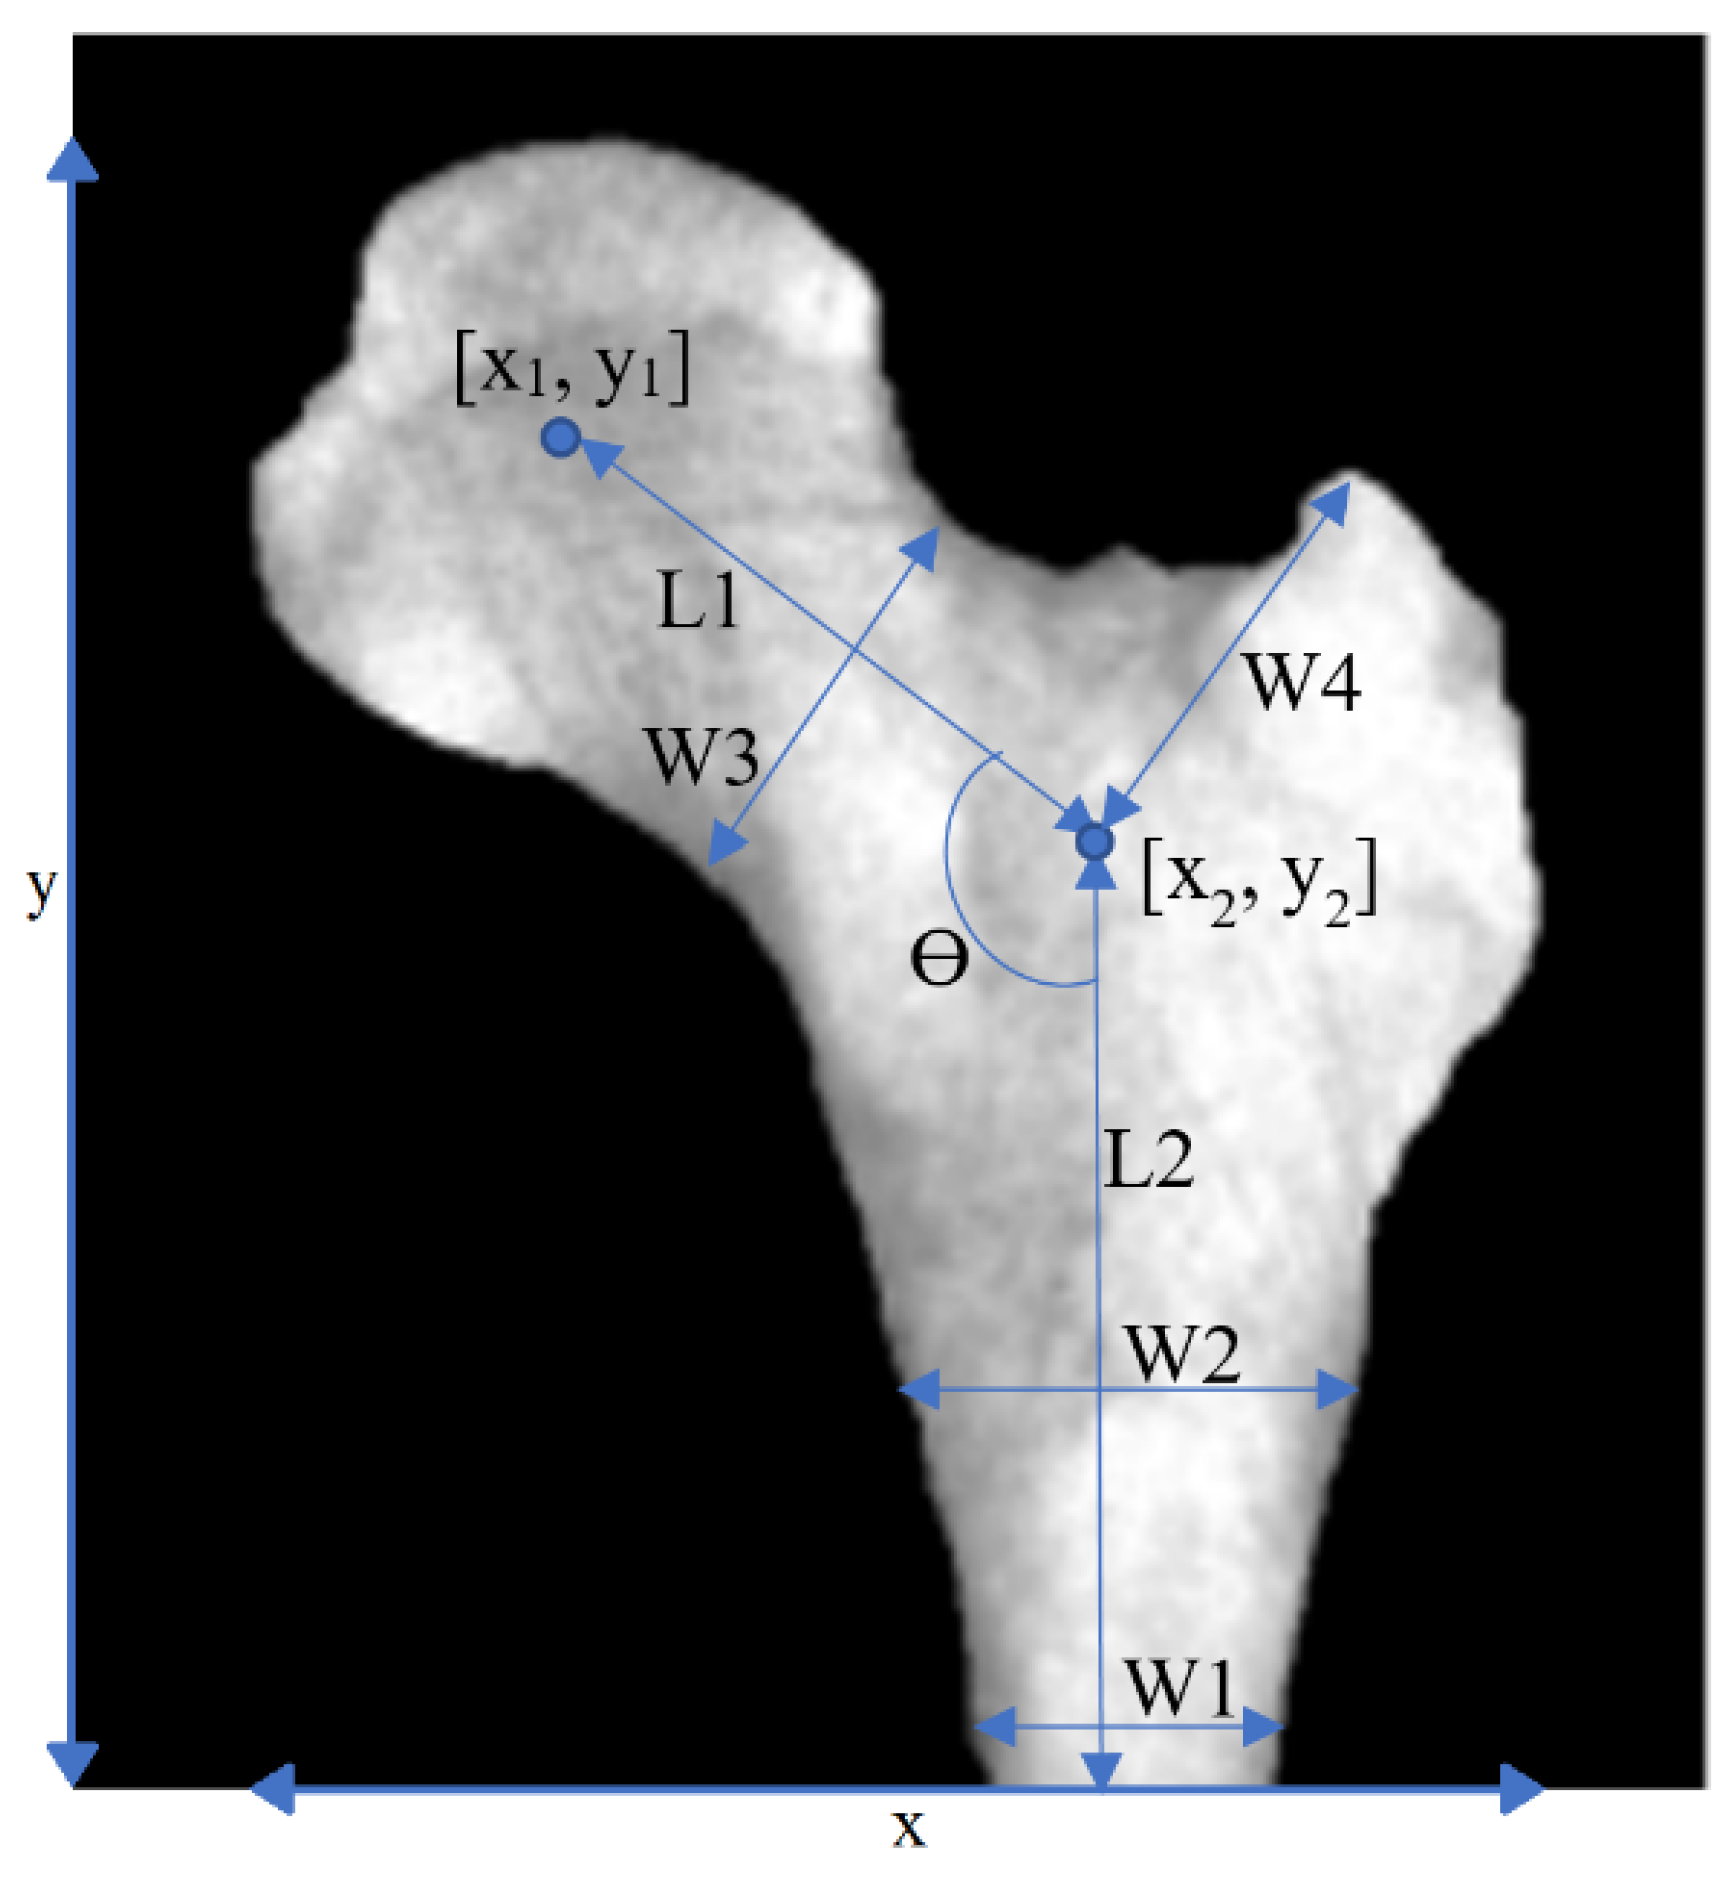

After segmentation, features were extracted. Figure 3 shows the basic geometrical features that were used in this study. The parameters W1, W2, etc. are defined as geometric features in Figure 3. The purpose of this definition of these geometric parameters that are marked on the figure was to find out whether there is a relationship between the defined geometric parameters with osteoporosis. To put it more simply, parameters W1, W2, etc. were defined by ourselves as geometric features and are not shorthand for a specific phrase or word.

Figure 3.

Geometrical features. Geometrical features extracted from a PFB image.

In SVM-Gaussian, the seven selected features were W0, C1-1 (max. of second derivative), C1-1 (variance) 2, C2-0 (first to last point ramp) 2, C4-0 (moment2 (ramp_removed_sig)) 2, and fractal dimensions. On the other hand, the main selected features for SVM-RBF were based on geometric features (15 features) and C2-0 (9 features). The most influential features in our study in descending order were geometrical features (in Table 1), C1-2, C2-0, fractal dimensions, C1-0, C1-1, and, finally, features based on the texture. The most-used features across all classifiers were y1, W2, and C1-1 (kurtosis (ramp_removed_sig)).